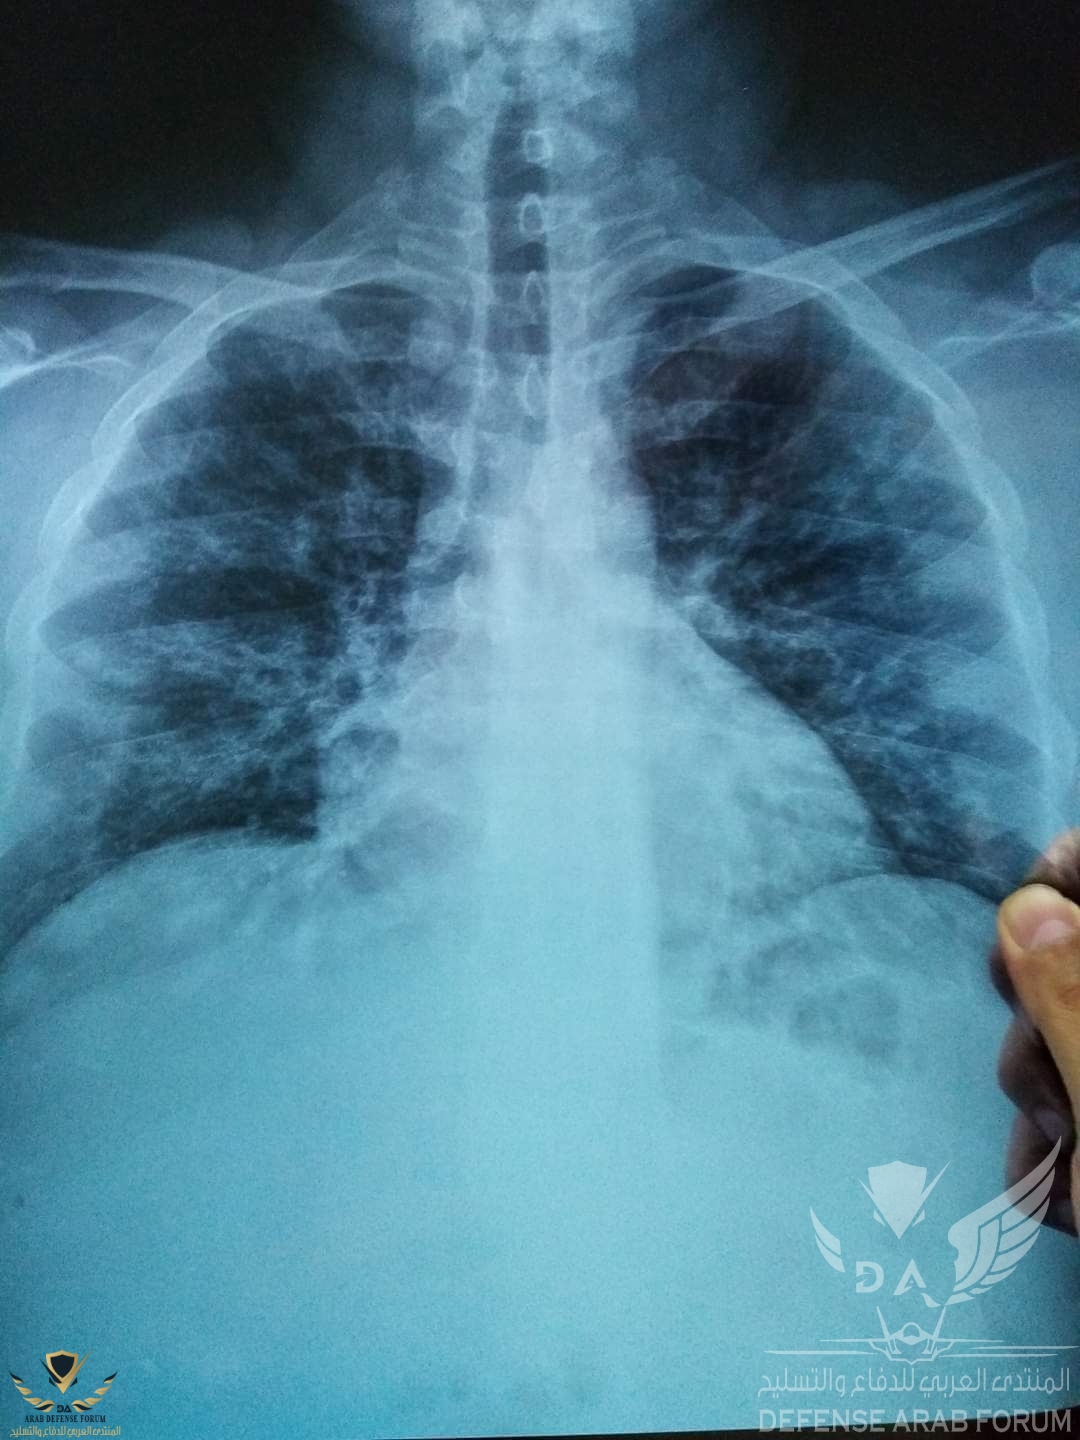

تجربة د.محمد سعيد طبيب الأطفال الذى شفاه الله من فيروس كورونا لتعم الفائدة ومرفق بها الاكس راى

- رابع يوم الصبح بدأت اعمل الاشعة اللي اظهرت

Bilat. Infilteration ( broncho Pneumonia)

وصورة الدم اللي أظهرت ..

Leukopenia 2.1

Hb 18%

Rbc 6.5 million

Platelets 87000

بالتالي بدأنا في العلاج قبل ظهور نتيجة المسحة ،،،، اللي طلعت فيما بعد سلبية ..